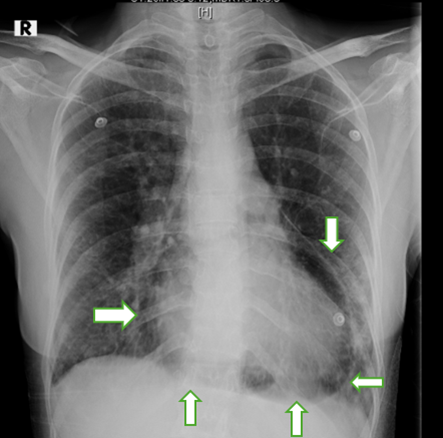

Next day the patient developed a pleuritic chest pain with respiratory distress with hypotension. Follow up chest radiograph showed a lucency around the cardiac silhouette with 'continuous diaphragm sign', limited superiorly by the cardiac pedicle, which was not seen in previous radiograph with reduction in cardiac size. (Figure 3). Emergency CT Thorax revealed pneumopericardium. (Fig 4) In view of pneumopericardium with hemodynamic compromise she was taken up for pericardiocentesis again and final flouro showed minimal residual air in the pericardial cavity. Recheck echo showed normal biventricular function and no features of cardiac tamponade. Subjective symptoms and radiological signs of pneumopericardium disappeared five days later. (Fig 5) The patient’s clinical syndrome was treated with steroids and antitubercular therapy.

Figure 3: Chest radiograph showing a lucency around the cardiac silhouette with ‘continuous diaphragm sign' (white arrow)

Clinical manifestations are variable and very unspecific like pain, dyspnea, palpitation. Sometimes patients could be asymptomatic making early detection of the disease before hemodynamic instability a real challenge.[6] Tension pneumopericardium can be fatal. Physical examination may show tachycardia, distended neck veins, and hypotension. Pathognomonic signs such as the mill wheel murmur “bruit de moulin” can be heard as a succession splash and traducing shaking movement of the heart within pericardial cavity on cardiac auscultation.[6] Chest radiographs reveal air as a radiolucent rim separating the pericardium from the heart, called “Continuous diaphragm sign.[7]